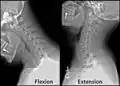

صورة بالأشعة السينية للفقرات العنقية في وضع الإنثناء و التمدد.